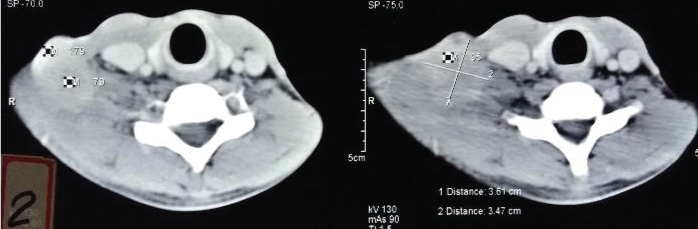

The patient came back after three years in December, 2015 with an ulcerated, hard fixed 8 cm x 6 cm nodal mass in the right supraclavicular region [Table/Fig-3]. A biopsy was done which showed metastatic nasopharyngeal carcinoma. The metastatic work up done was normal. As the nodal mass was inoperable, the patient was planned for reirradiation. The patient was treated to a dose of 40 Gy for 16 fraction i.e., 2.5 Gy per fraction, five days a week over three weeks by 3D Conformal Radiation Therapy (CRT) technique. There was a complete clinical response and the patient again defaulted.

Suggesting nodal recurrence.